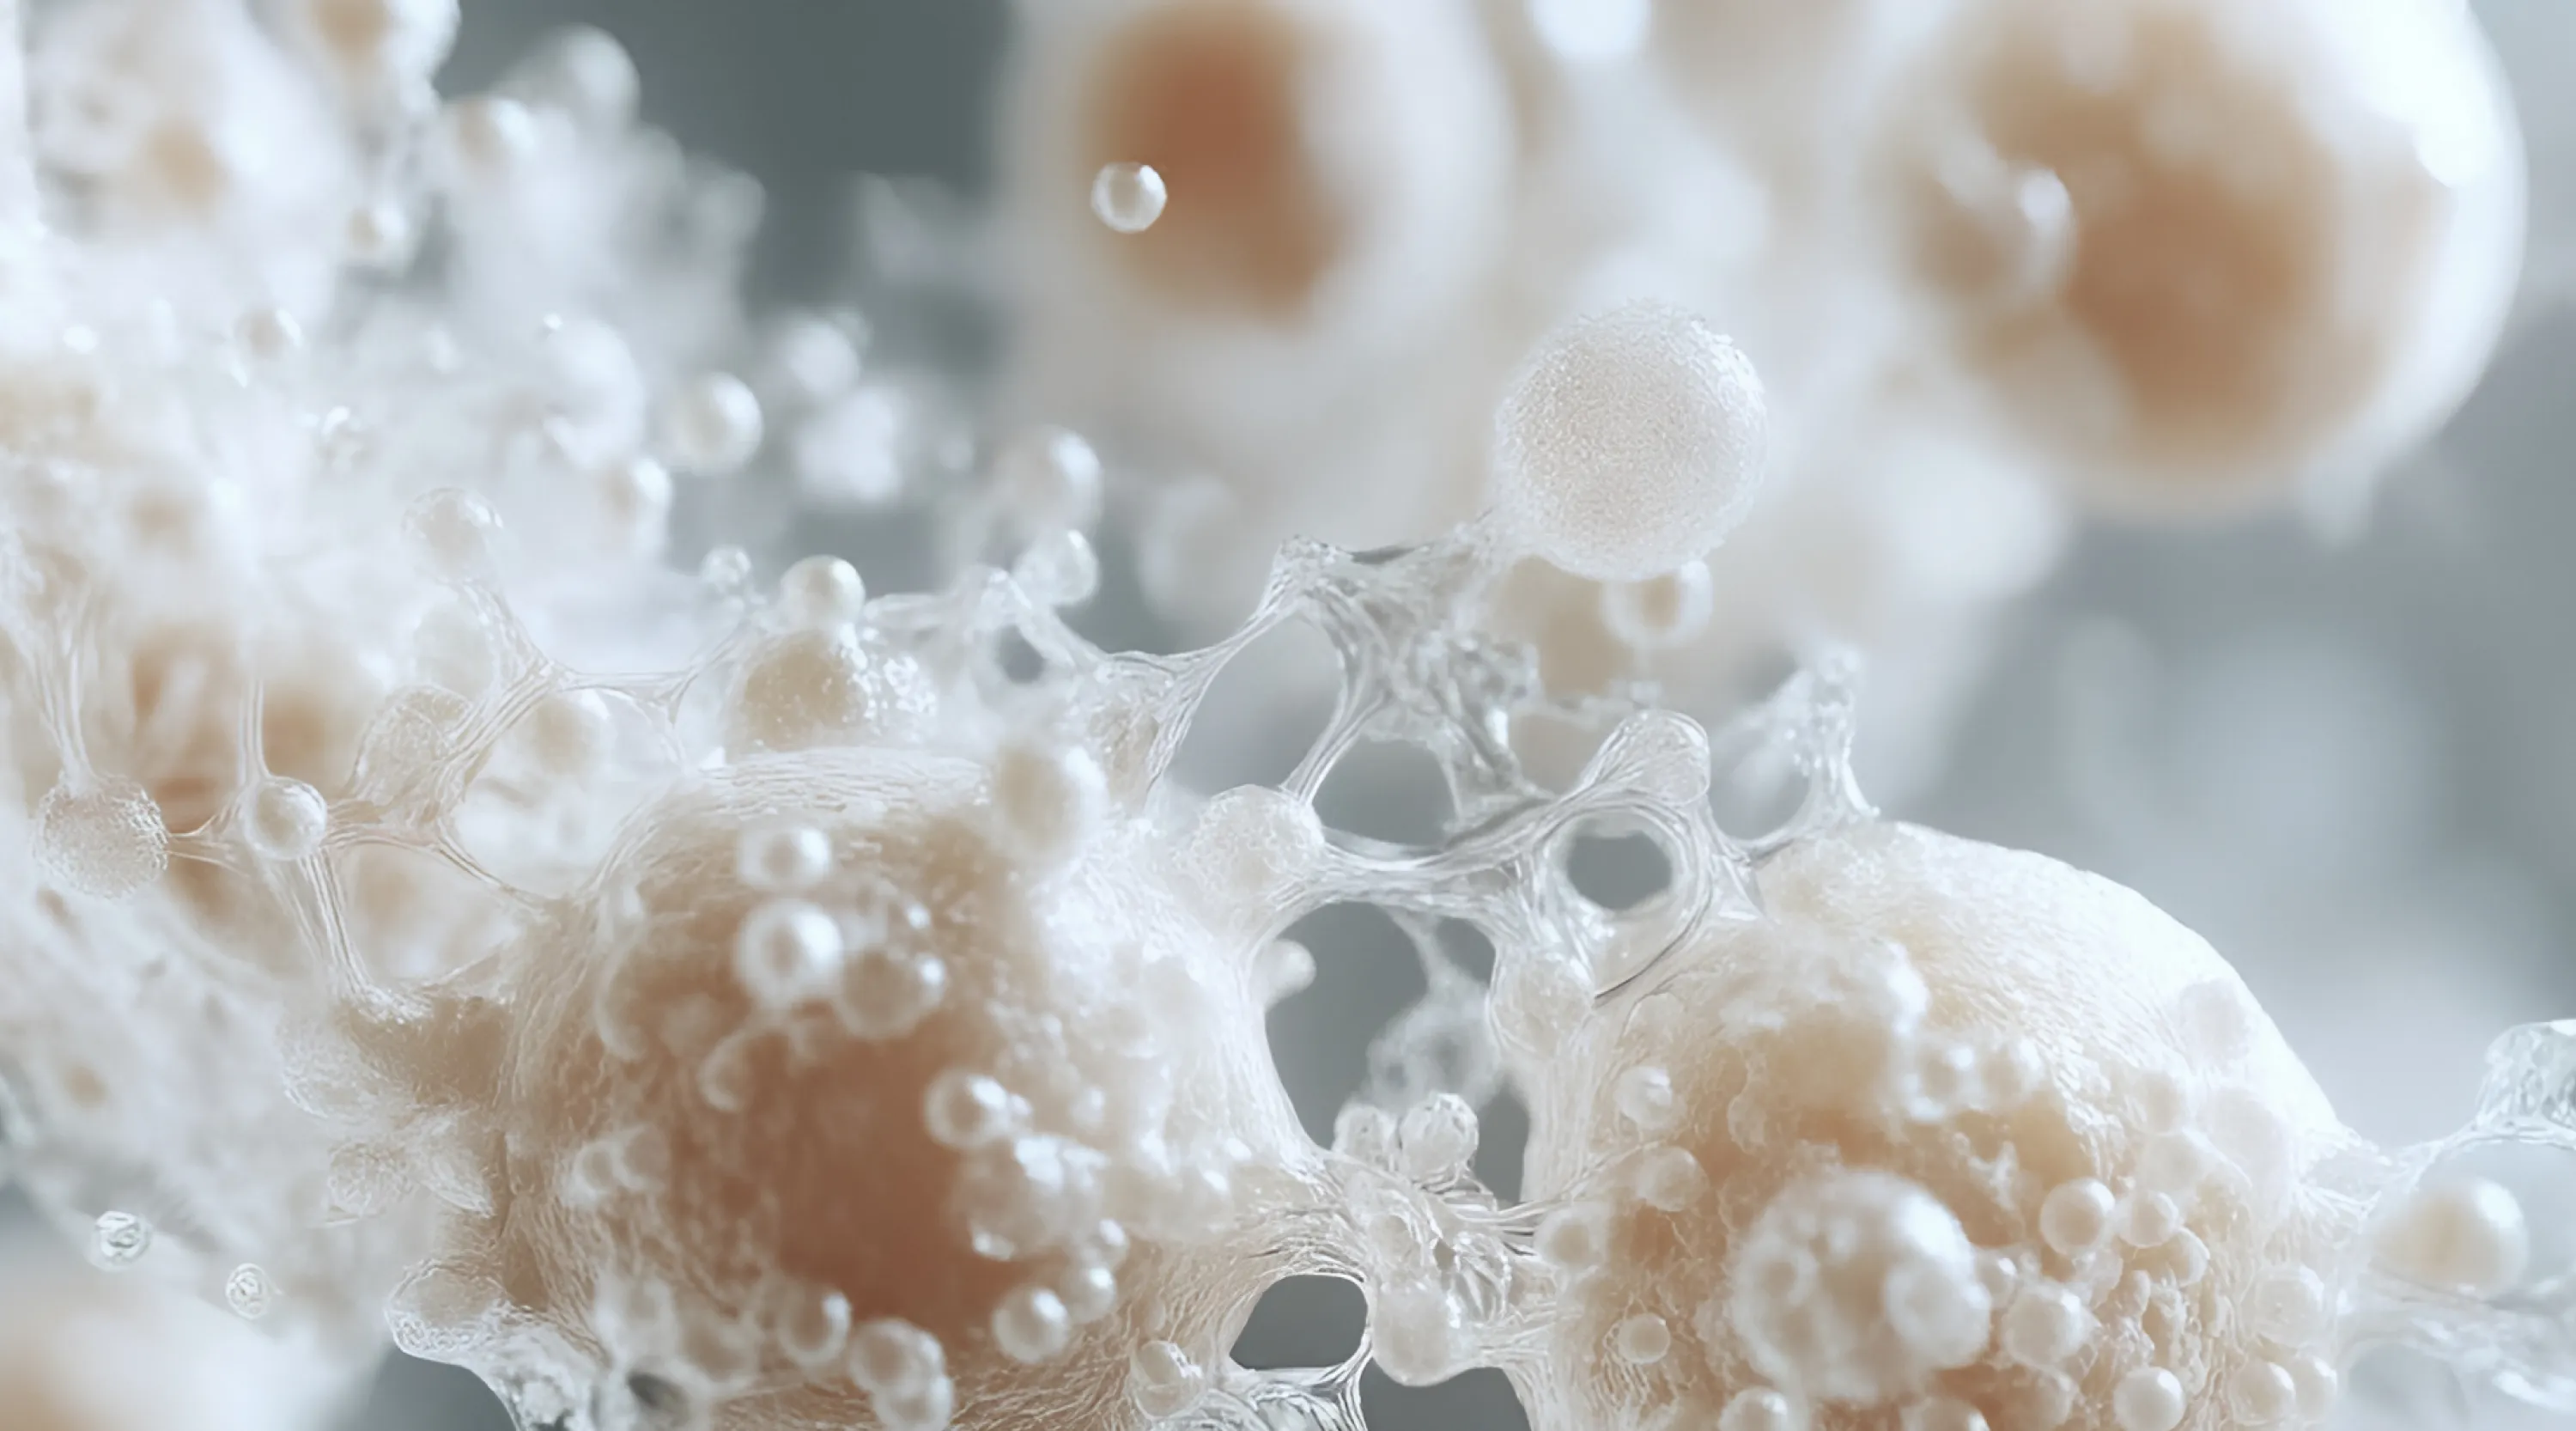

Эксклюзивный формат: Глубокое погружение и предметное изучение связочного аппарата лица и сосудистого компонента. Разбор осложнений. Отработка навыка. Баллы НМО.

Уникальный биоматериал: Последовательная диссекция тканей лица на качественном биоматериале (не более двух с учетом вариабельности пациентов.

- Подробное изучение связочного аппарата лица, сосудистого компонента.